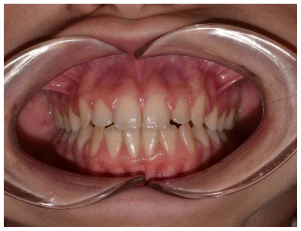

Case 2

The patient was a growing female child who presented during early mixed dentition with an anterior crossbite associated with a deep overbite and a marked sagittal discrepancy (Figures 12–19). The initial clinical examination revealed a negative overjet, complete anterior deep bite, and a functional Class III occlusal pattern. Extraoral assessment showed a flattened facial profile, while cephalometric analysis confirmed a skeletal imbalance characterized by increased SNA and SNB values, an ANB of 0°, negative Withs appraisal, and significant dentoalveolar compensations, including proclination of both upper and lower incisors (Table 3). The vertical pattern was predominantly hypodivergent, suggesting a high risk of unfavorable mandibular growth progression if left untreated. Given the patient’s young age and growth potential, an early interceptive treatment was planned to use the AMCOP® TC appliance, with the aim of correcting the anterior crossbite, improving neuromuscular balance, and guiding sagittal and vertical development during growth. The appliance was worn nightly and for additional daytime hours, according to patient compliance.

After 18 months of treatment, a clear clinical improvement was observed. Intraoral examination demonstrated complete correction of the anterior crossbite, with establishment of a positive overjet and normalization of the anterior occlusal relationship. The deep bite was reduced, allowing more functional anterior guidance. Occlusal relationships improved toward a stable dental Class I, and the need for excessive dentoalveolar compensation was reduced. Cephalometric reassessment showed an overall improvement in sagittal relationships and incisor inclinations, with a trend toward normalization of the previously altered parameters. These findings indicate that early functional therapy with the AMCOP® TC appliance was effective in intercepting the developing Class III malocclusion, improving occlusal function, and potentially reducing the severity of future skeletal discrepancies (Table 4).